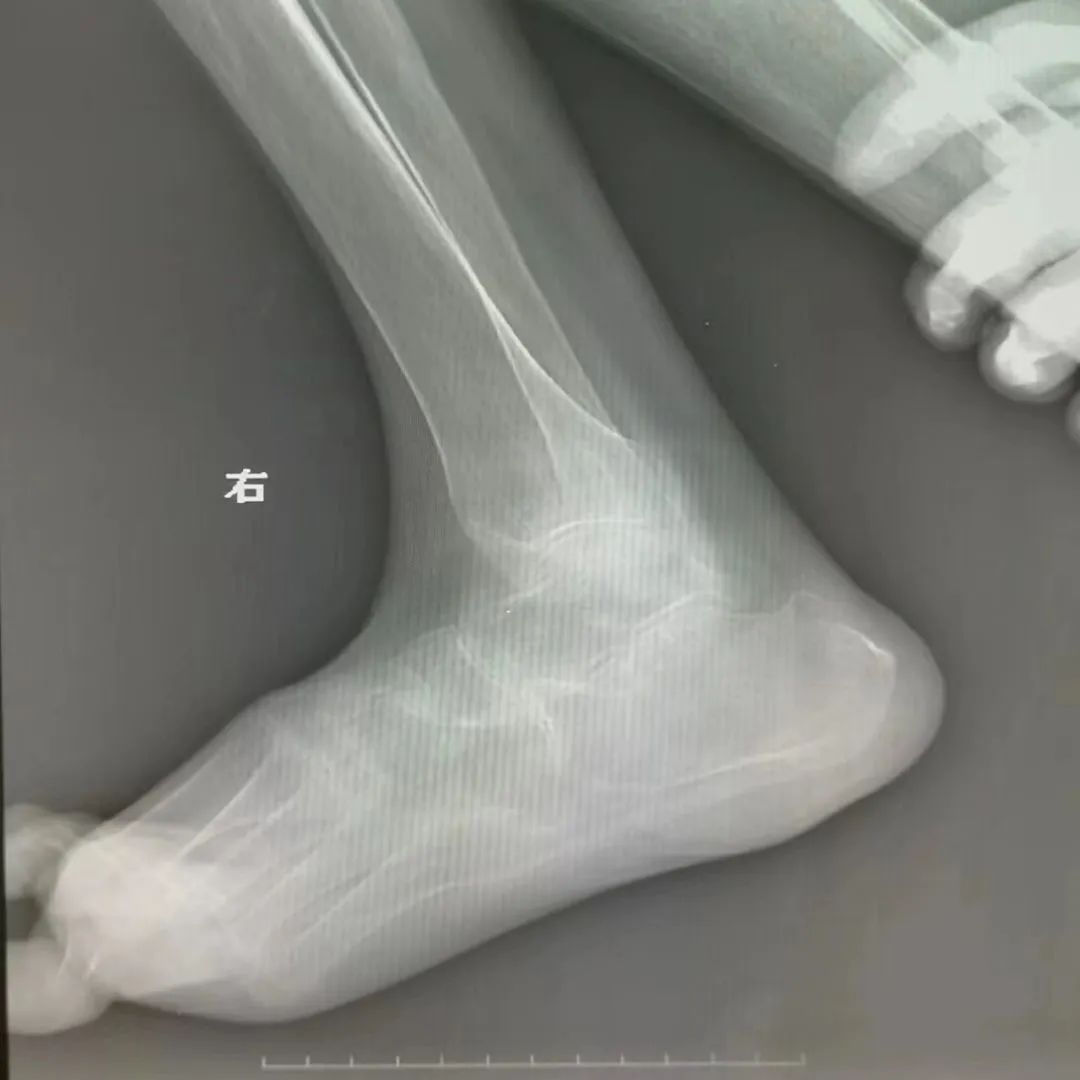

该患者伴有严重的类风湿性关节炎并肢体畸形

经过细致的检查评估,曹玮主任决定采用目前国际上较为成熟的“脊髓电刺激”疗法来为张阿姨治疗糖尿病足性疼痛,并避免截肢。脊髓电刺激治疗是一种微创疼痛治疗技术,它是在脊髓的硬膜外后间隙插入一根电极,通过电刺激阻断疼痛信号的传导,同时可调控交感神经以改善糖尿病足的末梢血运循环。但是由于张阿姨长期患有类风湿性关节炎,脊柱及四肢严重畸形,无法俯卧位,且椎管多节段狭窄,常规操作无法将电极植入脊椎预定位置,为治疗带来了很大难度。为此,曹玮主任及其团队决定创新采用血管鞘介入技术辅助电极植入,用穿刺针成功引入导丝、导管及血管鞘,通过血管鞘成功建立电极植入通道,之后成功将电极植入至硬膜外脊髓背侧预定的相应刺激区域。在术中测试及术后随访中,张阿姨表示下肢疼痛明显减轻。